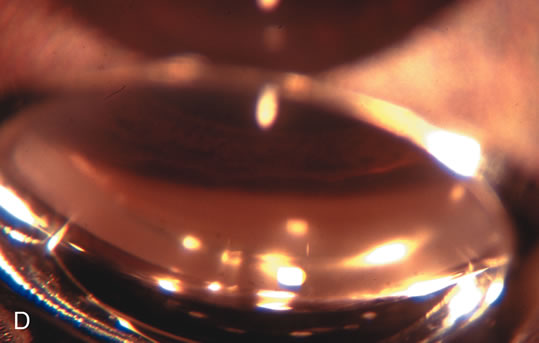

Fig. 5. Anterior chamber angle changes associated with lens extraction and PCIOL This 65-year-old Vietnamese woman has a long-standing history of chronic angle-closure glaucoma treated with laser peripheral iridectomy. The optic nerve demonstrated mild glaucomatous damage and IOP was moderately controlled on two antiglaucoma medications. The cataract was removed through temporal clear corneal phacoemulsification with foldable acrylic IOL. A. Symptomatic cataract in narrow-angle glaucoma eye with patent iridectomy. B. Intraoperative goniophotograph showing crowding of angle with increasing narrowness due to phacomorphic component. C. Intraoperative photograph showing temporal clear corneal approach with IOL in the capsular bag. D. Intraoperative goniophotograph demonstrating deepening of chamber angle following lens extraction. Proposed theories for IOP reduction following lens extraction with complete wound closure:

1. Anterior chamber deepening with improved access to trabecular meshwork

2. Increase in traction on the trabecular meshwork

3. Improved outflow facility mediated by an increase in prostaglandin release

4. Reduction in aqueous humor production

5. Atrophy of ciliary body processes

6. Goniosynechialysis due to intraoperative over deepening of AC with viscoelastic

7. Relief of undiagnosed pupil block